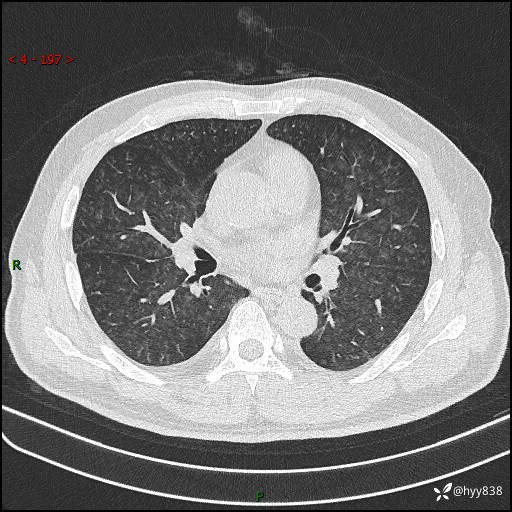

辅助检查:CT

胸部HRCT